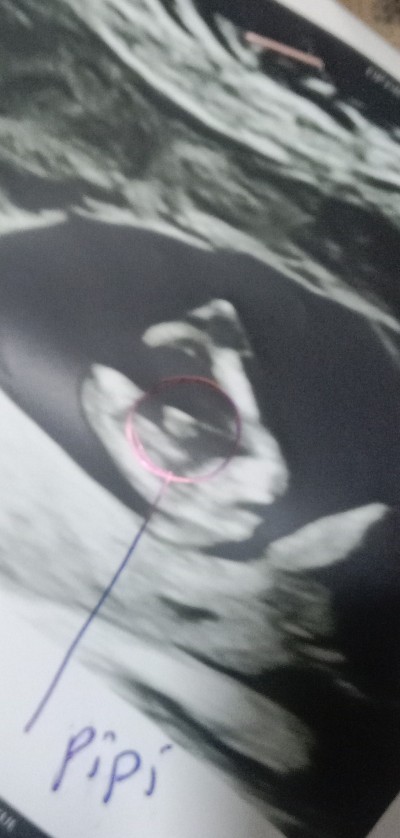

Bizim bu seki bacak arasi

image

Yan yuklendi resim